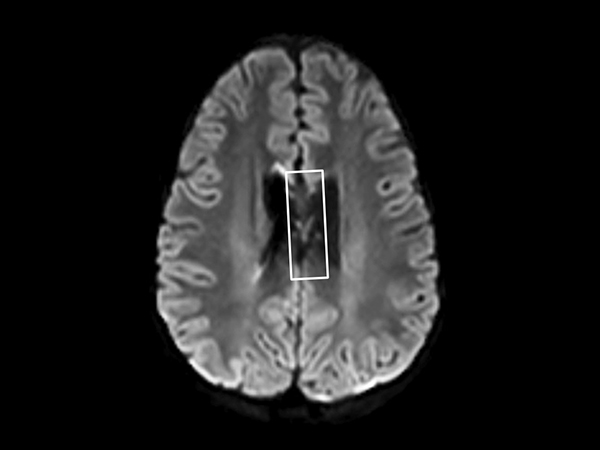

In this case, a 10-year-old girl thrown from a horse. The SWIp images provided increased visibility of the corpus callosum injury compared to the T2-weighted, diffusion weighted and gradient echo images, see the box in the images. SWIp also provides increased visibility of the cortical contusion (arrows) compared to gradient echo imaging. In this case, SWIp helped to characterize the extent of the patient’s injury, which is important to know for short term care and longer term prognosis and rehabilitation.

Axial SWIp